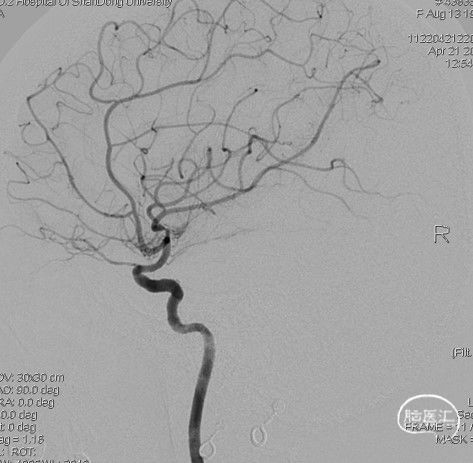

病人甲的影像资料:

造影:右侧颈内动脉末端变细,大脑前及大脑中自起始部闭塞,脑底少量烟雾血管形成,汇聚使R-MCA少量分支显影。

右侧颈内动脉正位: